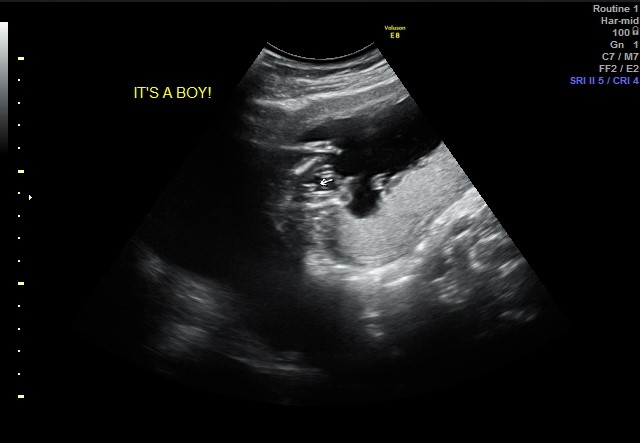

I had an early elective ultrasound yesterday at 14 weeks and 5 days. Baby was measuring at 15 weeks and the tech said boy. Is she correct? Am I having a boy??

I'm really hoping it's a boy!Attachment 41053Attachment 41052

It looks boyish but I know the 14th week can be so tricky with gender determination, and even the 15th week is early. When will you be getting another scan?

I had two 15 week gender scans en this is a boy! Obvious

it looks boyish but being only 14w makes me unsure, if that was a 16w pic id be saying 100% boy :) fingers crossed this is your boy!!

funnily enough ive just seen another thread with a 14w potty shot where the tech guessed 70% girl, i dont trust 14w potty shots i think it is too early but.. that thread showed a potty shot with nothing between the legs, compare it to yours and there is a world of difference, fingers crossed for you! :)

To the original poster: This is a boy to me. Congrats! I have done a lot of googling on this and I saw a 14 min lecture by Dr. Mahir on youtube about gender determination.

Thought I would update everyone. Blood work confirmed that I'm having a boy!! I'm over the moon excited! :D